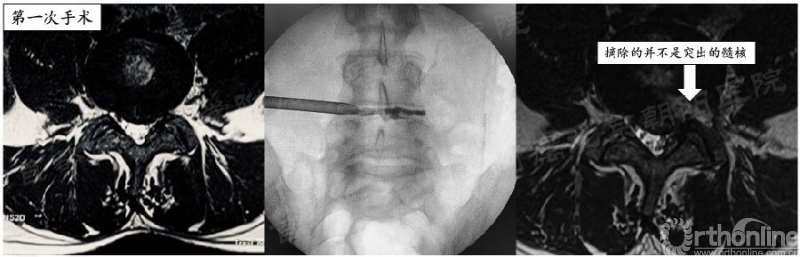

我就不做或做不好成型会怎样呢?举一例反面病例,也是前30例中唯一因手术效果不佳行二次手术的患者:

患者33岁美籍白人男性,L4/5节段II区突出,第一次手术由于通道角度不理想,同时未行充分关节突成型,未能将突出的髓核摘出,手术效果不理想。在二次手术时调整通道方向,同时行3级关节突成型,实现了对神经的彻底减压(见视频6-1,6-2)。